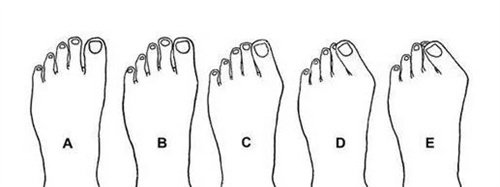

困扰多年的双脚难题

我的双脚大脚趾根部长期以来一直向外突出,形成难看的骨凸。不仅穿鞋经常磨脚,走路时间稍长就会隐隐作痛。每到夏天,我总是避免穿凉鞋,担心别人看到我变形脚型的异样眼光。这种困扰像块沉甸甸的石头压在我的心头,让我渴望找到解决之道。